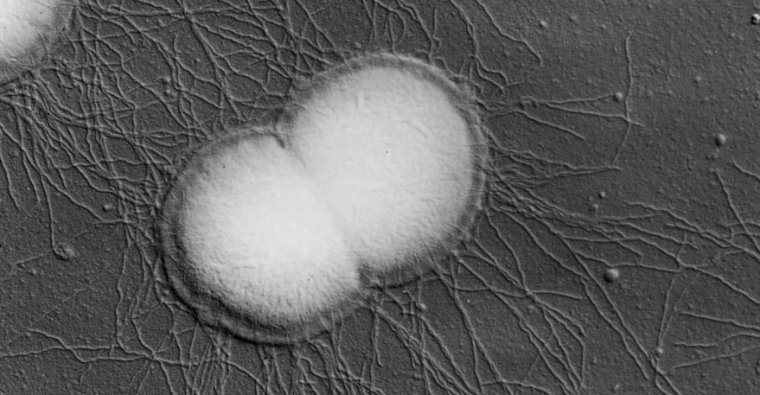

A scanning electron micrograph of Neisseria gonorrhoeae.

Enlarge / A scanning electron micrograph of Neisseria gonorrhoeae. (credit: NIH)